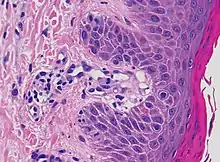

| Mycosis fungoides | Present | Focal | Regular or irregular | Normal | Normal | Minimal or no spongiosis; ±Pautrier microabscess | Atypical lymphoid cells lining the dermo–epidermal junction | ![]() Pautrier microabscesses |